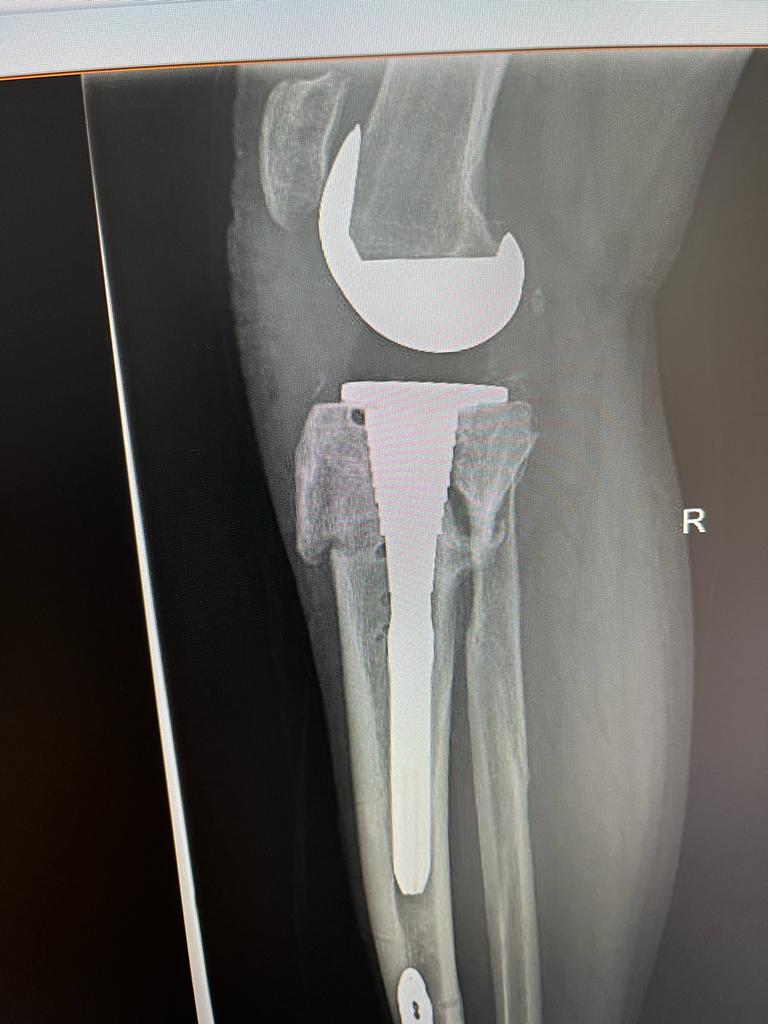

„Tinand cont de varsta tanara a pacientului, am optat la o versiune necimentata a endoprotezei și augmentarea la nivelul tibiei proximale (unde prezenta intarziere in consolidare si stoc osos precar) cu un con metalic Porocoat pentru a facilita si stimula osteoinductia. De asemenea, femurul si tija centromedulara tibiala care preia tensiunile din genunchi sunt necimentata. Acest dispozitiv protetic ne-a fost adus special pentru acest caz de firma Johnson and Johnson careia ii mulțumim. Totodata multumim si echipei operatorii și colegilor anesteziști”.

Rezultatul postoperator a fost un succes, s-a reusit alinierea genunchiului, dr. CHIREA MARIUS, medic primar ORTOPEDIE-TRAUMATOLOGIE obtinand o proteza necimentat primara stabila si cu mobilitate maxima.